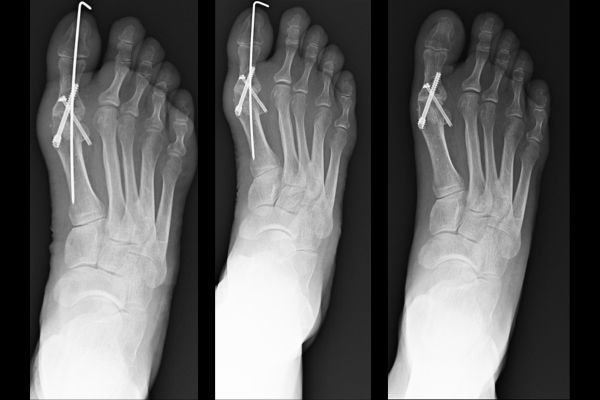

Accelerate Post-Surgical Healing

Alleviate post-operative pain and swelling while accelerating recovery times.

• Post-Surgical Recovery